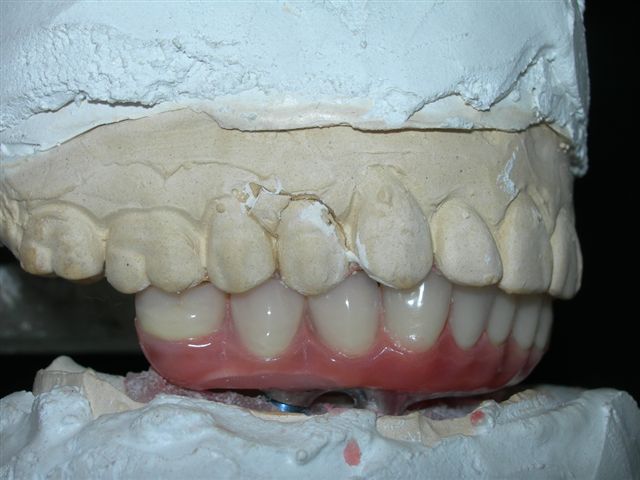

Estudo para estabelecimento da articulação dentária e dimensão vertical (VISTA FRONTAL)

Prova de articulação pós acrilização (fase laboratorial) |

Prova de articulação após acabamento (fase laboratorial) |